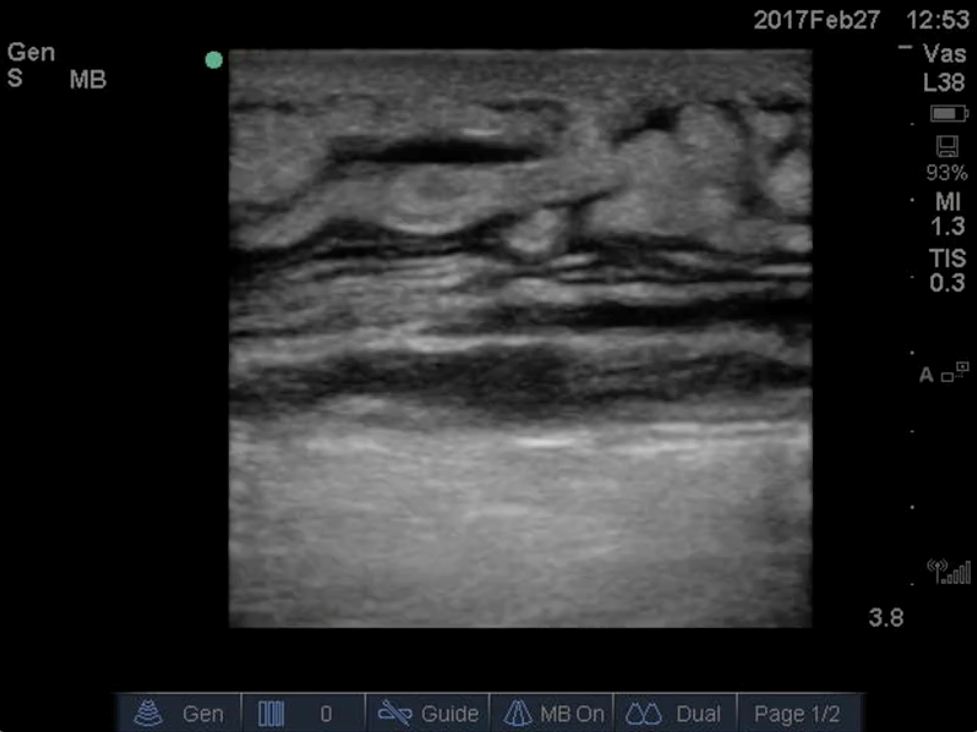

Anechoic or hypoechoic fluid within the tendon sheath and thickening of tendons are highly suspicious for pyogenic flexor tenosynovitis in the appropriate clinical context. Compare this with the cobblestone appearance of cellulitis on ultrasound.

Flexor tenosynovitis. Note the fluid collection within the flexor tendon sheath. Courtesy of Dr. Shirley Wu.